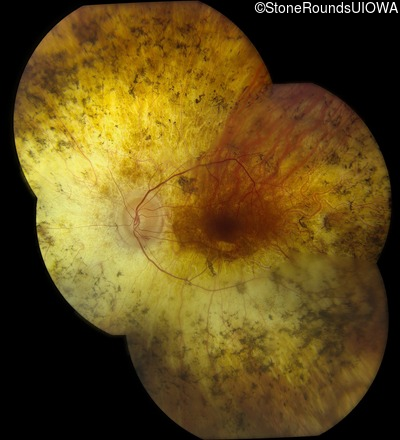

Fundus Montage - Right - 20/40 -1 sc

Exemplar